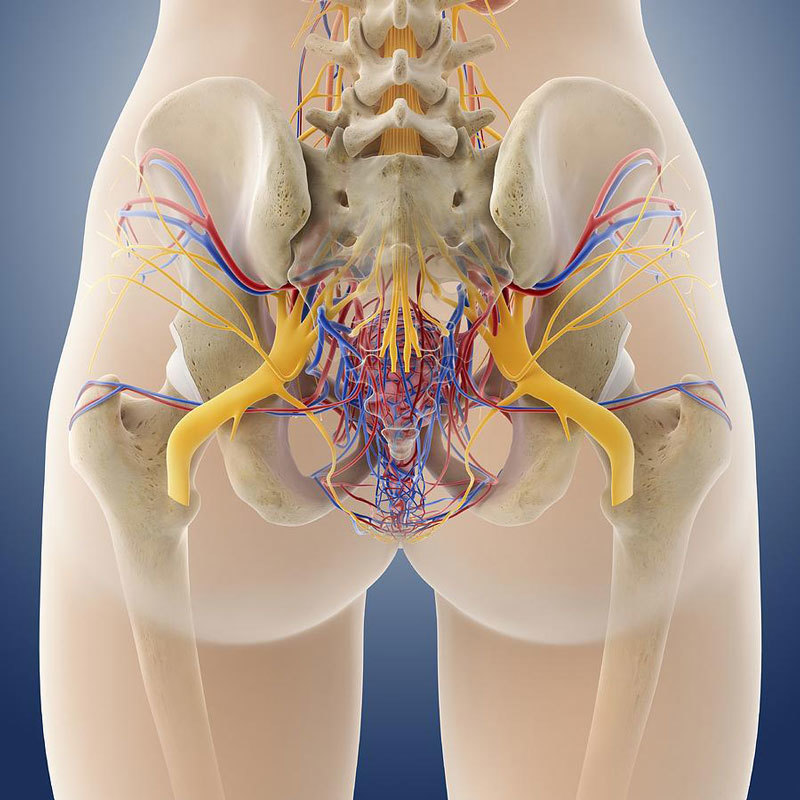

Анатомия малого таза: детальные схемы и изображения